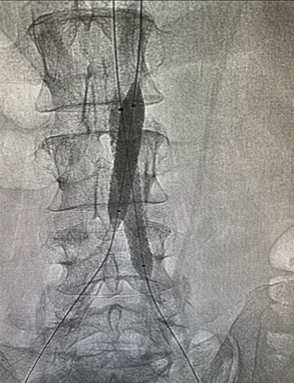

Aortografía con colocación de stents

En situaciones moderadas o severas, procedimientos mínimos invasivos se pueden llevar a cabo como angioplastia, la dilatación de estas zonas con un balón intravascular, con la colocación de stent. Los stents son un tipo de resorte que, generalmente, comprime la placa hacia la pared y crea una luz más amplia del vaso sanguíneo.